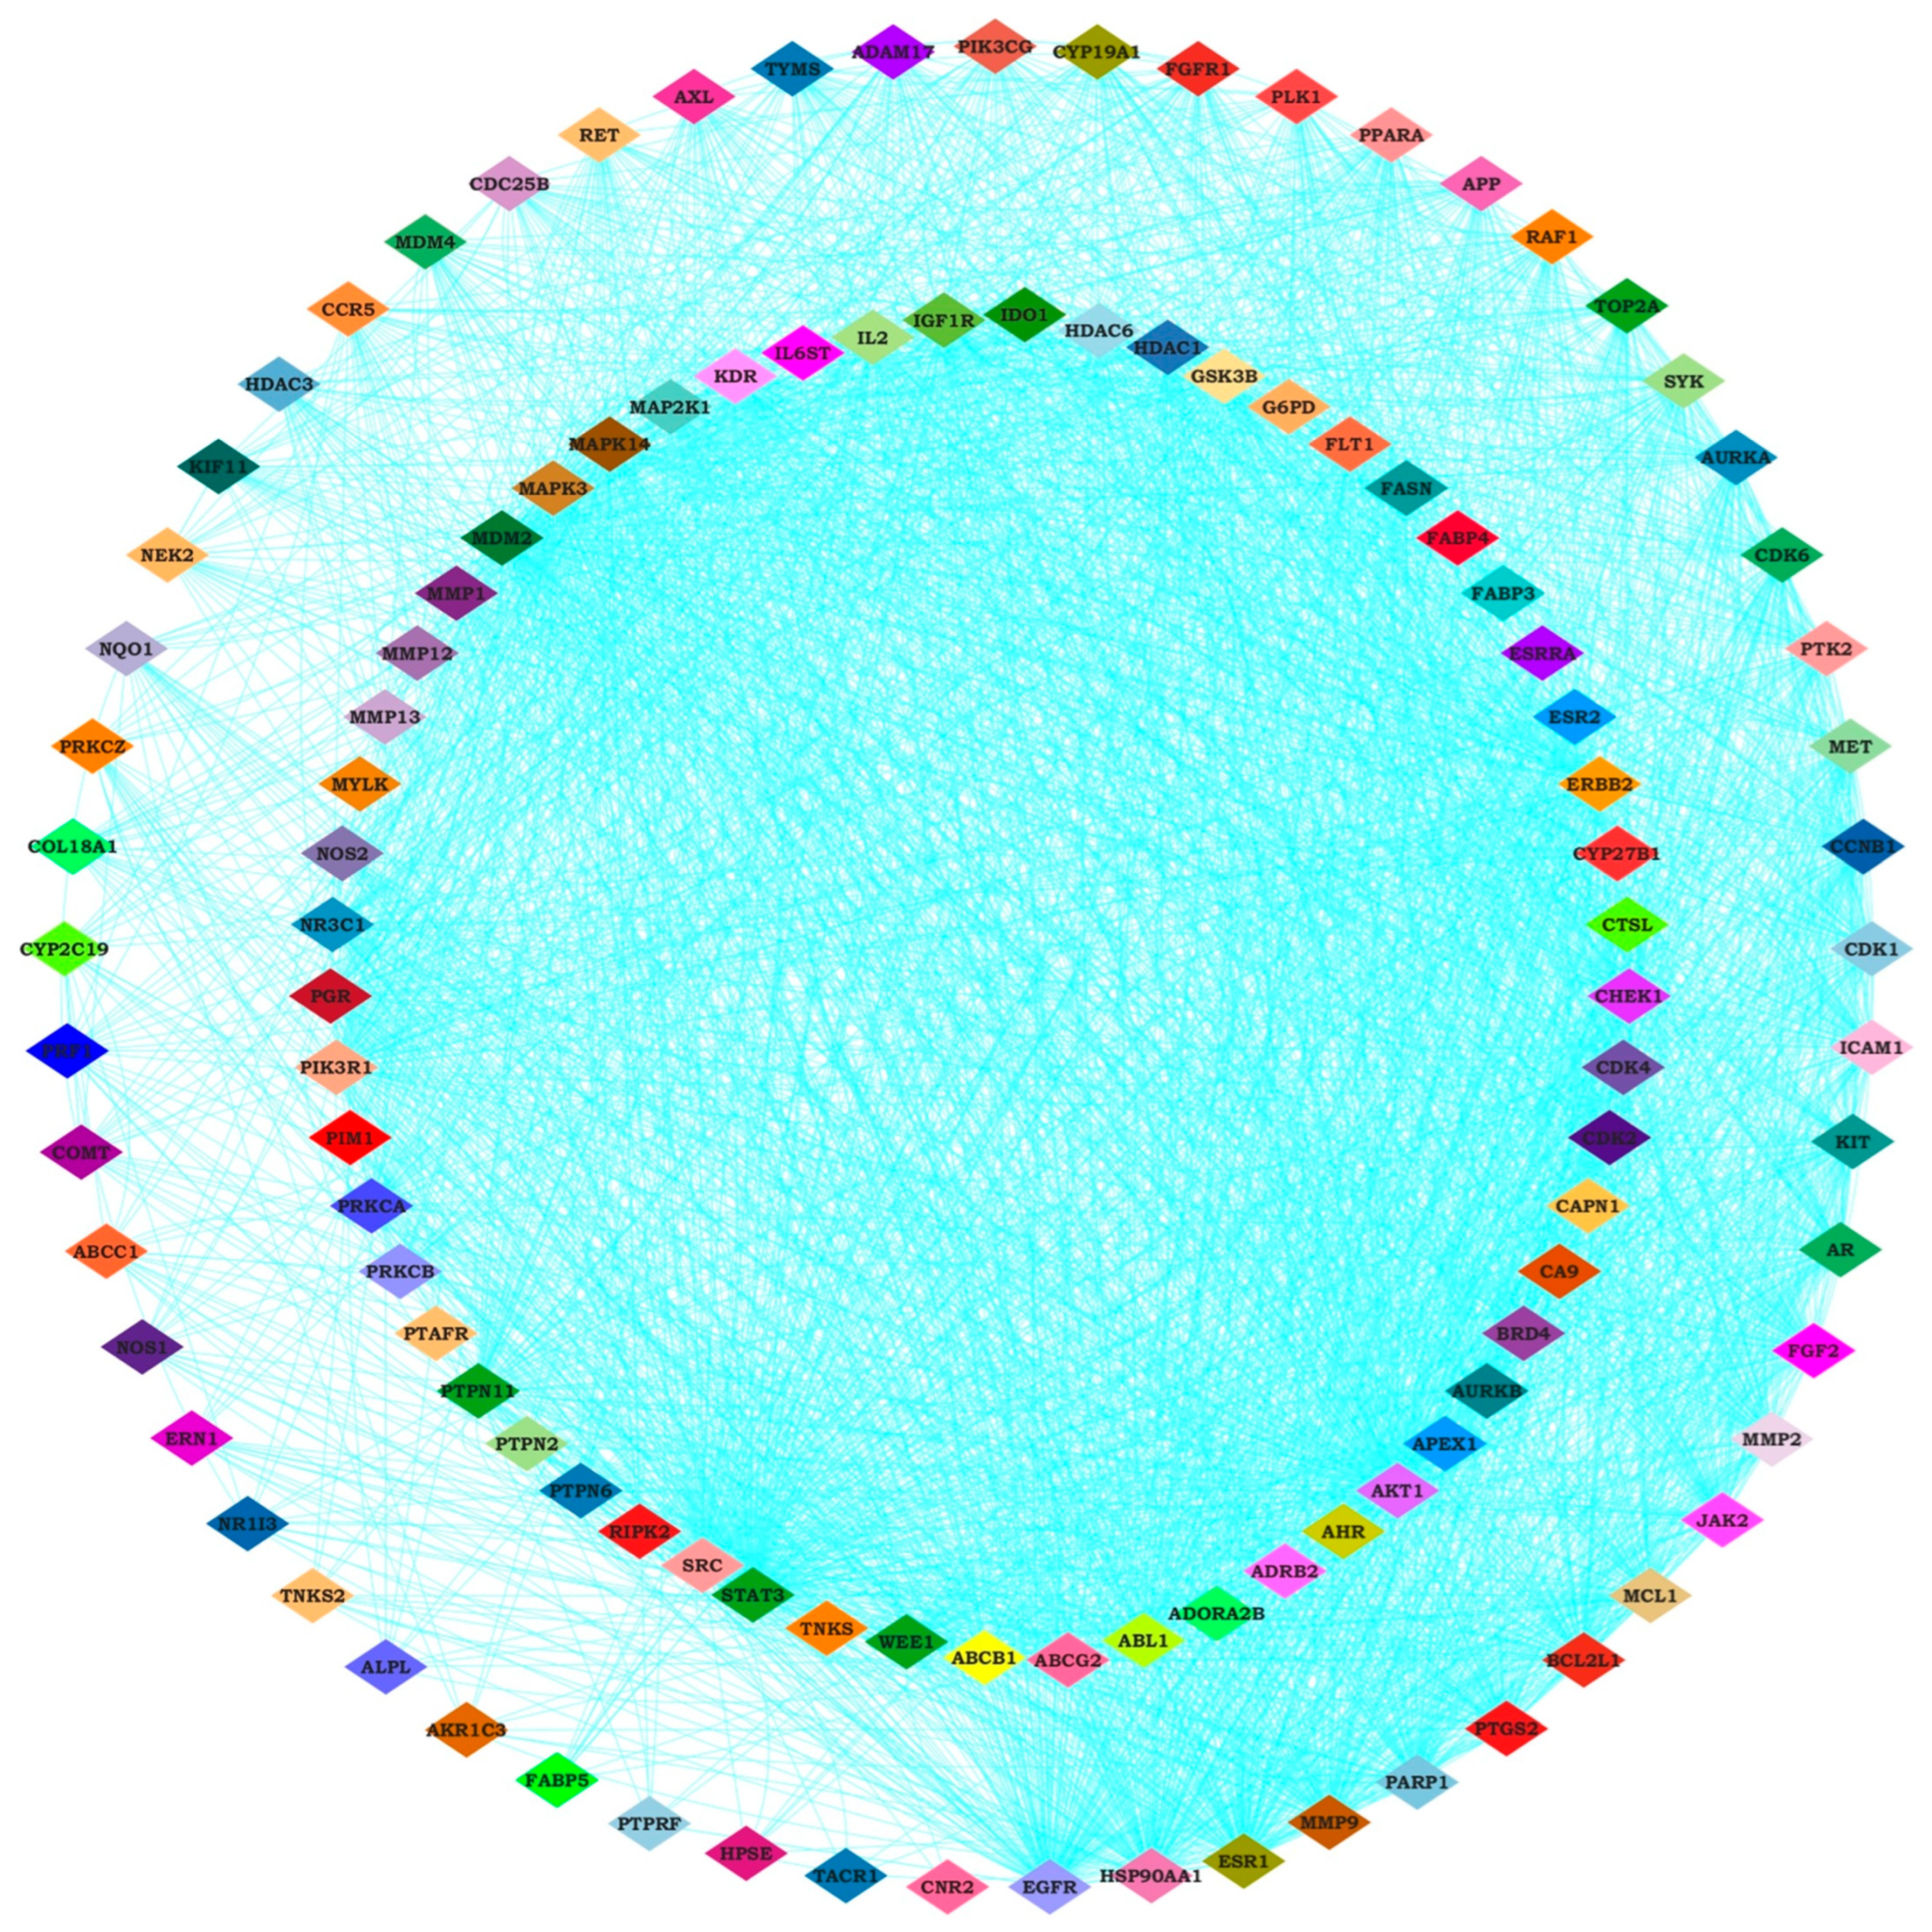

2.3. Identifying Hub Genes and Construction of Compounds-Disease Common Target Network

4.4. Hub Gene Identification and Protein Interaction Network Analysis